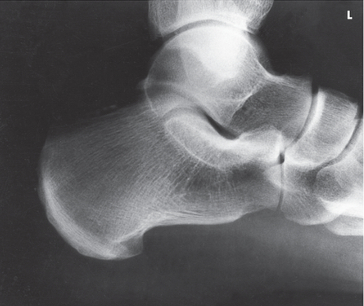

Name this projection.

Lateral foot

What type of projection is it?

Mediolateral

On which side should the patient be positioned?

Affected side

What 2 things should be ⟂ to the IR?

Patella and plantar surface

Where does the CR enter?

Perpendicular to the base of the 3rd metatarsal

What is shown in profile?

The entire foot

How can you guarantee that the foot is in a true lateral position?

Place your hand perpendicular to the IR and line the foot up with your hand to obtain a true lateral; if you do not do this, the foot will be over-rotated, and the malleoli/metatarsals will not superimpose properly

How can you tell if the foot is in a true lateral?

Open sinus tarsi, metatarsal superimposition, fibula superimposes tibia on posterior half